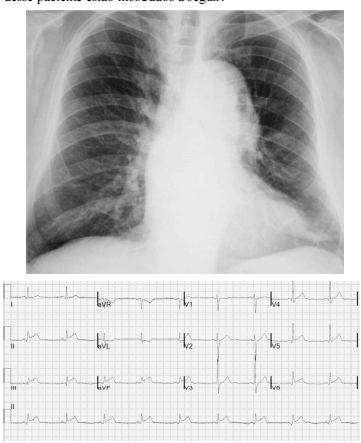

Um paciente de 68 anos de idade e hipertenso apresentava dor torácica lancinante na parede anterior com irradiação para a região cervical, de forte intensidade e sem alívio com analgésicos comuns havia duas horas. No exame físico, ele se encontrava sudorético e acianótico, com saturação de oxigênio em ar ambiente de 90%, pressão arterial de 182 mmHg × 112 mmHg e frequência cardíaca de 88 bpm. Apresentava ritmo cardíaco regular em dois tempos, com sopro diastólico (+/4) no segundo espaço intercostal à direita. Os valores da troponina ultrassensível foram normais. A radiografia de tórax e o eletrocardiograma desse paciente estão mostrados a seguir.

Com relação ao caso clínico hipotético anterior, julgue o item que se segue.

Recomenda-se o uso de nitroprussiato de sódio para a redução de até 25% da pressão arterial média em uma hora.

Um paciente de 68 anos de idade e hipertenso apresentava dor torácica lancinante na parede anterior com irradiação para a região cervical, de forte intensidade e sem alívio com analgésicos comuns havia duas horas. No exame físico, ele se encontrava sudorético e acianótico, com saturação de oxigênio em ar ambiente de 90%, pressão arterial de 182 mmHg × 112 mmHg e frequência cardíaca de 88 bpm. Apresentava ritmo cardíaco regular em dois tempos, com sopro diastólico (+/4) no segundo espaço intercostal à direita. Os valores da troponina ultrassensível foram normais. A radiografia de tórax e o eletrocardiograma desse paciente estão mostrados a seguir.

Com relação ao caso clínico hipotético anterior, julgue o item que se segue.

A angiografia coronariana é o método de escolha para a confirmação diagnóstica.

Um paciente de 68 anos de idade e hipertenso apresentava dor torácica lancinante na parede anterior com irradiação para a região cervical, de forte intensidade e sem alívio com analgésicos comuns havia duas horas. No exame físico, ele se encontrava sudorético e acianótico, com saturação de oxigênio em ar ambiente de 90%, pressão arterial de 182 mmHg × 112 mmHg e frequência cardíaca de 88 bpm. Apresentava ritmo cardíaco regular em dois tempos, com sopro diastólico (+/4) no segundo espaço intercostal à direita. Os valores da troponina ultrassensível foram normais. A radiografia de tórax e o eletrocardiograma desse paciente estão mostrados a seguir.

Com relação ao caso clínico hipotético anterior, julgue o item que se segue.

A origem desse processo é explicada por ruptura de ateroma com grande atividade proteolítica, núcleo lipídico e necrótico proeminente, o que resulta na formação de um trombo sobrejacente.

Um paciente de 68 anos de idade e hipertenso apresentava dor torácica lancinante na parede anterior com irradiação para a região cervical, de forte intensidade e sem alívio com analgésicos comuns havia duas horas. No exame físico, ele se encontrava sudorético e acianótico, com saturação de oxigênio em ar ambiente de 90%, pressão arterial de 182 mmHg × 112 mmHg e frequência cardíaca de 88 bpm. Apresentava ritmo cardíaco regular em dois tempos, com sopro diastólico (+/4) no segundo espaço intercostal à direita. Os valores da troponina ultrassensível foram normais. A radiografia de tórax e o eletrocardiograma desse paciente estão mostrados a seguir.

Com relação ao caso clínico hipotético anterior, julgue o item que se segue.

A dupla antiagregação plaquetária e a heparina não fracionada devem ser iniciadas na admissão.